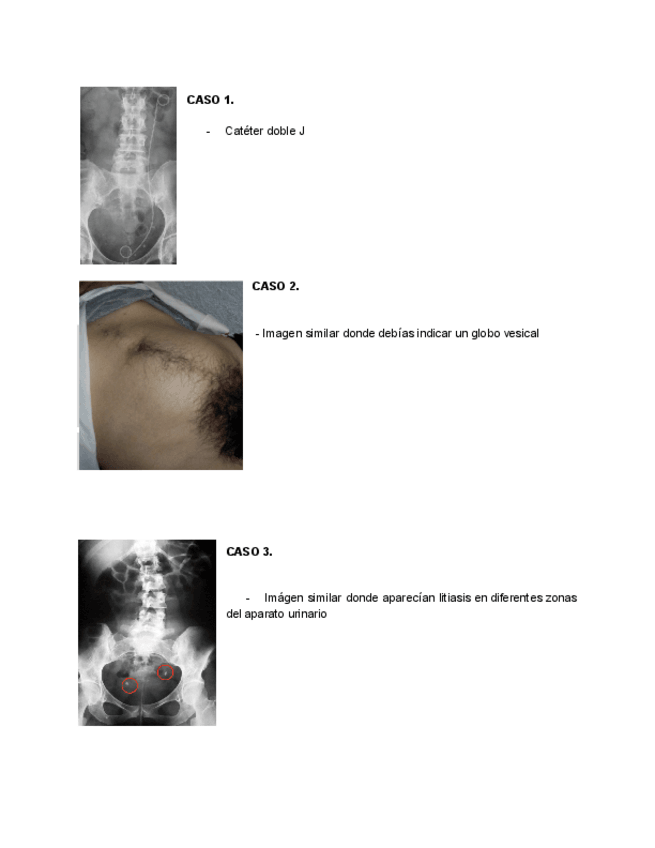

He publicado nuevos apuntes de 4º Nefrologia y Urología: Examen-practico-urologia-2025.pdf